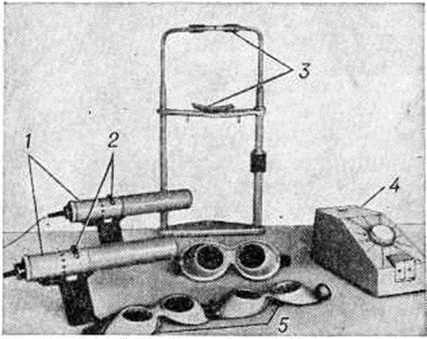

Приборы для исследования и лечения косоглазия и амблиопии делятся на четыре группы: плеоптические — для исследования и лечения дисбинокулярной амблиопии; ортоптические — для исследования и лечения нарушений бинокулярного зрения; стереооптические — для исследования и восстановления глубинного и стереоскопического зрения; группа приборов для исследования и лечения двигательного аппарата глаз.

Для проведения плеоптического лечения служат: большой безрефлексный офтальмоскоп Б 0-58 со специальными приставками (СССР), плеоптофор (Швейцария) и комплект из двух ручных офтальмоскопов — визускопа и эйтископа (ФРГ). Большой безрефлексный офтальмоскоп Б 0-58 снабжён фиксационной иглой для установки амблиопичного глаза в требуемом положении, тангенциальной шкалой с затемняющим шариком для определения участка неправильной фиксации и малогабаритной лампочкой накаливания для локального «слепящего» и стимулирующего воздействия светом на центральную ямку сетчатки по методу Аветисова. Плеоптофор — стационарный офтальмоскоп с лампой-вспышкой для «ослепления» участка сетчатки с неправильной фиксацией и низковольтовой лампой для стимулирующего засвета жёлтого пятна. Визускоп предназначен для определения положения фиксирующего участка амблиопичного глаза с помощью тангенциальной шкалы, а эйтископ для лечения амблиопии методом отрицательных последовательных образов.

Для частичного или полного выключения глаза из акта зрения при лечении амблиопии применяют окклюдоры. В СССР для этой цели выпускается окклюдор универсальный ОКУ-1 в виде пластмассовой пластины с круглым проёмом для установки окклюдирующей заслонки (непрозрачной или с отверстием разной формы).

Для закрепления результатов лечения амблиопичного глаза методами плеоптики применяют прибор для тренировки зрения при амблиопии (СССР), локализатор-корректор (Швейцария), хейроскоп (СССР, ЧССР), макулотестер поляризационный (СССР), координатор (ФРГ), центрофор (Швейцария) и ряд других приборов.

Макулотестер поляризационный, координатор и центрофор применяют для перевода зрительной фиксации, близкой к центральной, в центральную. Прибор хейроскоп представляет собой разделитель полей зрения для развития центрального одновременного зрения и бинокулярного зрения.

Приборы для исследования и лечения двигательного аппарата глаз применяются для определения функциональный состояния глазодвигательной мышцы или групп мышц методом коордиметрии, для исследования и развития подвижности и конвергентных движений глаз, для контроля эффекта операции на глазодвигательных мышцах. Метод коордиметрии в СССР проводится с помощью прибора офтальмокоордиметра ОКМ-1 (рисунок 7). Для исследования и развития подвижности глаз предназначен прибор «Мускултренер» (СССР). Для исследования и развития конвергенции в СССР выпускается прибор под названием «Конвергенцтренер».